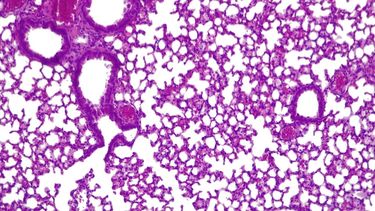

La lucha contra el cáncer de pulmón El 17 de noviembre se conmemora el día mundial de la lucha contra el cáncer de pulmón, el propósito es crear conciencia en la población sobre la importancia de prevenir la enfermedad 17 de noviembre de 2020 - 08:30